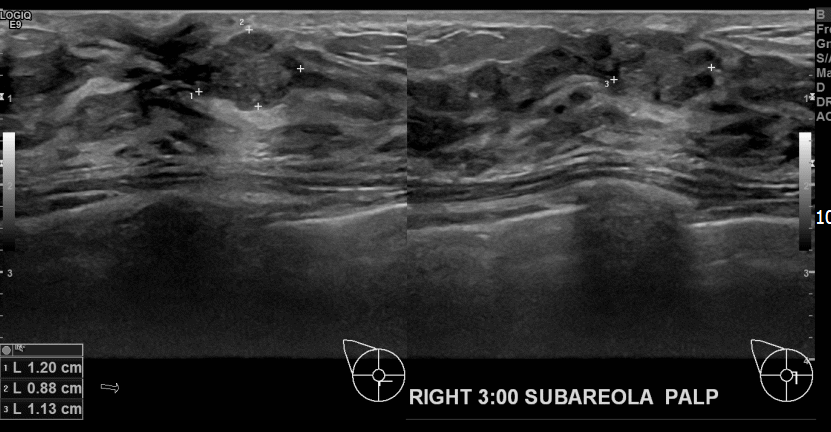

상기환자 만져진멍울있어 내원하신 20대여성분으로 우측유방

의심스러운 혹 조직검사시행후 유방암 진단되었습니다